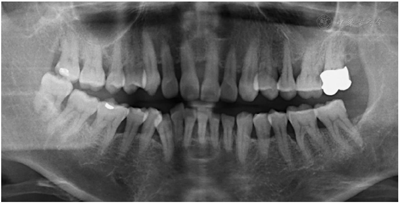

全口临床检查:口腔卫生状况一般,菌斑、软垢少量,下前牙舌侧可见新生牙石,龈下牙石(++)。牙龈色偏红,肿胀,形态圆钝,质软,尤以下前牙舌侧为重,出血指数3~4。全口牙齿探诊深度(PD)5~7 mm,个别位点8~9 mm。全口牙齿均可探及附着丧失,21、24、25、41、43松动I~Ⅱ。46合面金属色充填体,27烤瓷冠复体,近中悬突,可见食物嵌塞,叩痛(-)。咬合关系深覆合,下前牙多生牙,下前牙区拥挤,43位置颊倾,反合,见图1,图2,图3。

全口影像学检查:12~22、25~26、34~36、45~46牙槽骨吸收进一步加重,但下颌出现骨白线,26远中冠部低密度影像近髓腔,根尖周无低密度影像。